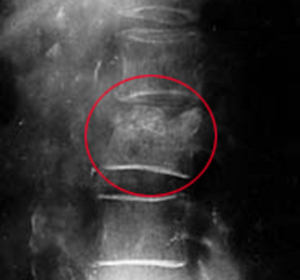

При туберкулёзе костей позвоночника заболевание начинается сначала в одном позвонке. При этом во время развития гранулёмы происходит разрушение самой костной ткани, а воспалительный процесс постепенно переходит на другие позвонки. Происходит сильная деформация позвоночного столба и сдавление косного мозга, при котором начинают формироваться парезы и параличи, вылечить которые бывает практически невозможно.

Костный туберкулёз легко обнаруживается при рентгенологическом исследовании костей. При этом можно обнаружить все очаги разрушения костной ткани, секвестры и даже абсцессы. Для диагностики очень важно получить кусочек отмершей кости. Это необходимо для того, чтобы определить в ней наличие микобактерий.